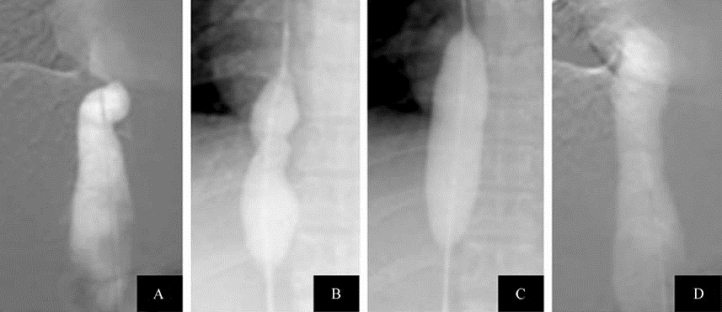

图21-19 Budd-Chiari综合征球囊血管成形术(一)

A.下腔静脉造影示下腔静脉右心房入口处严重狭窄,几乎闭塞;B.球囊扩张中,狭窄处尚未完全扩开;C.狭窄处已经完全扩开;D.下腔静脉造影复查示下腔静脉管腔增粗,血流通畅